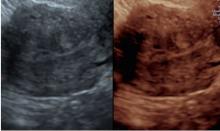

Immagini in 3d di adenocarcinoma endometriale in cui si denota un’infiltrazione del miometrio inferiore al 50% dello spessore miometriale e assenza di coinvolgimento dello stroma del canale cervicale.